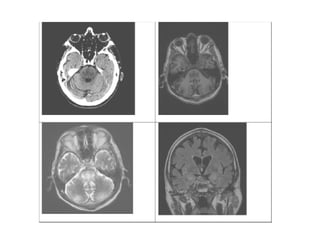

Unenhanced CT head

focal hypoattenuation in the mid and dorsal pons

MRI brain

abnormal low T1 and high T2 mexican hat shaped signal within the central pons

with sparing of the corticospinal tracts ventrolaterally.

Abnormal increased T2 signal was also demonstrated

in the thalami and putamen bilaterally

Restricted diffusion was noted in these corresponding regions

with diffusion weighted imaging (DWI)

Clinical and radiological findings were compatible with

central pontine myelinolysis (CPM)